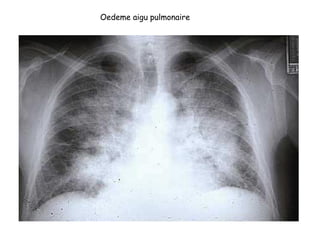

1. Radiographie thoracique : Oedème alvéolaire

Opacités diffuses, bilatérales, cotonneuses, a contours flous, peri-

hilaires, symétriques, « en ailes de papillon »

Oedeme aigu pulmonaire